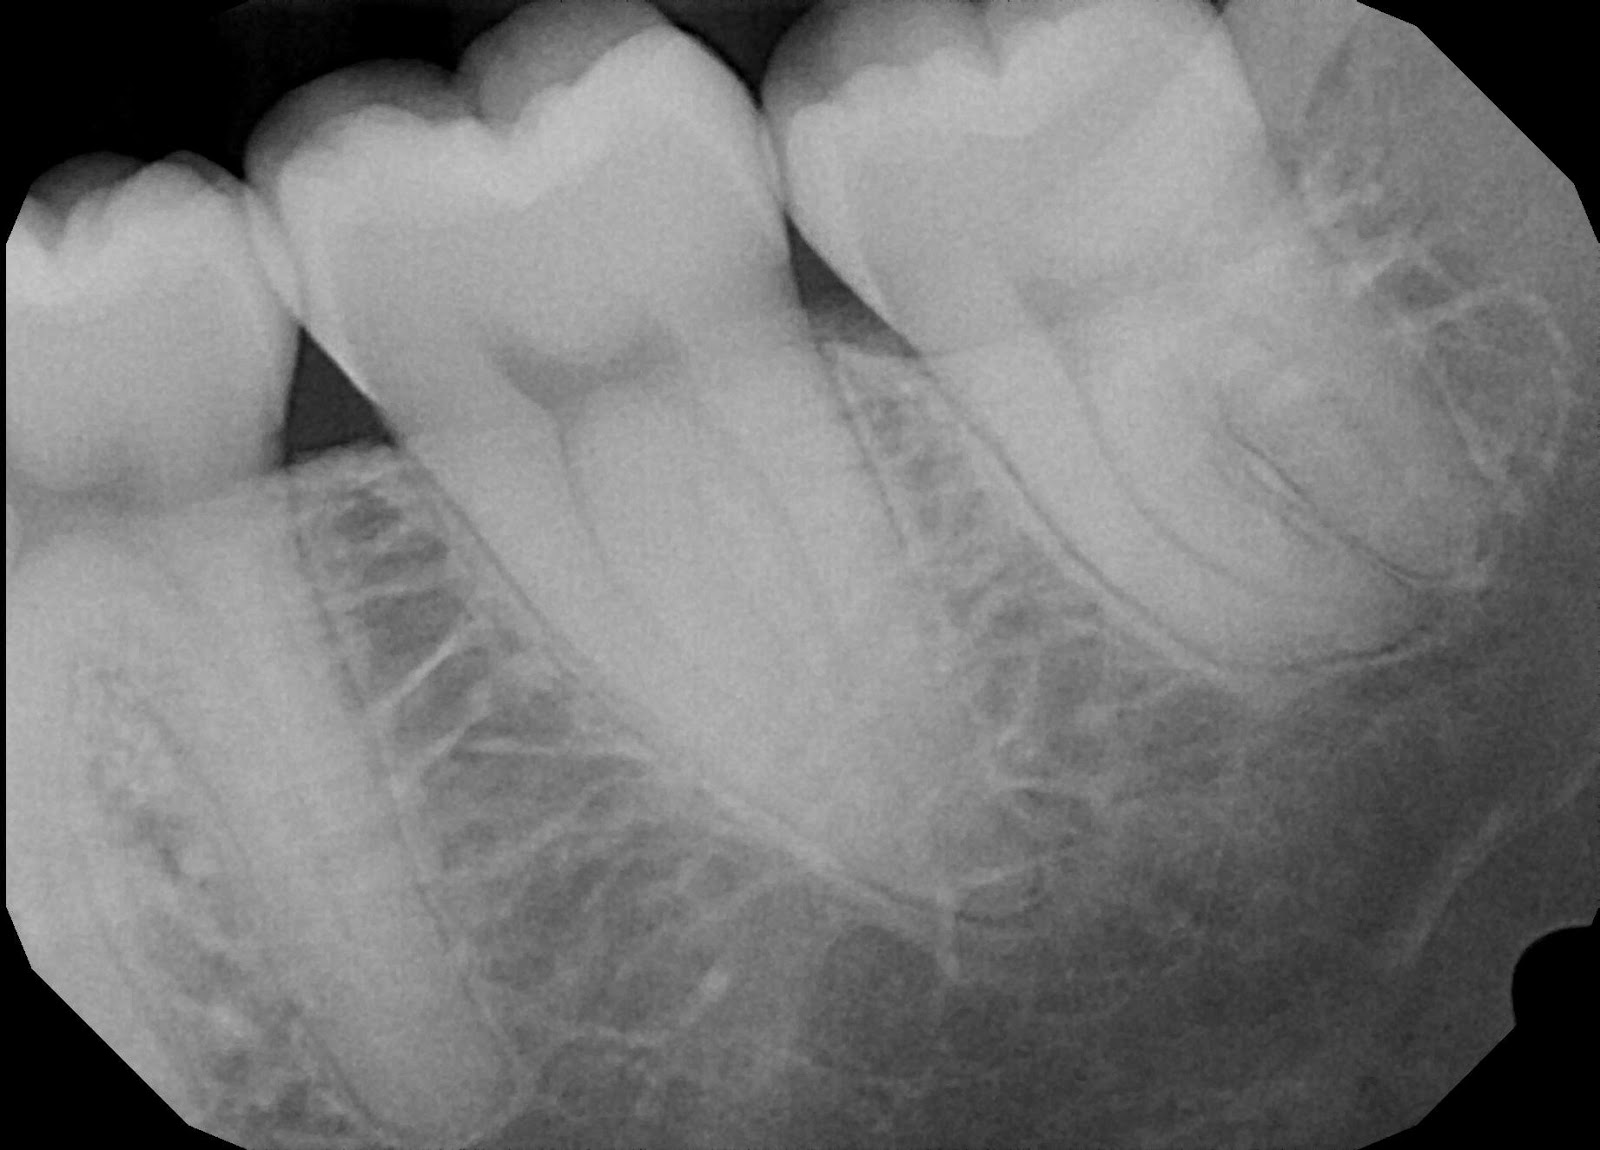

Jaws have also changed over time – becoming smaller – and leaving little room for wisdom teeth. With this change, wisdom teeth often impact or block teeth around them, which can cause complications. The American Association of Oral and Maxillofacial Surgeons estimate that up to 85 percent of wisdom teeth need to be extracted. Impacted wisdom teeth pose serious problems for the rest of the mouth and can result in pain, infection, and cavities. X-rays are most effective in diagnosing problematic wisdom teeth. For instance, it may seem that a tooth may have erupted, however, instead it is pushing into another molar. Wisdom teeth that do not erupt can also cause issues such as crowding, displacement of teeth, gum disease, damage to adjacent teeth, or in extreme cases cysts or tumors.